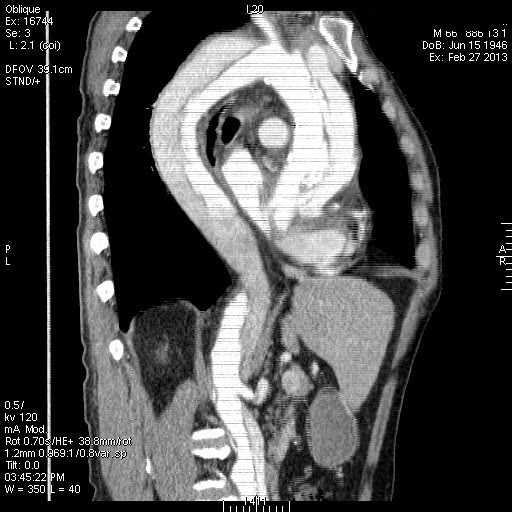

Расслаивающая аневризма аорты, Дебейки I

Пожилой пациент с жалобами на боли в грудной клетке. Болеет неделю.

Диссекция аорты 1 типа по DeBakey , Стенфорд А .